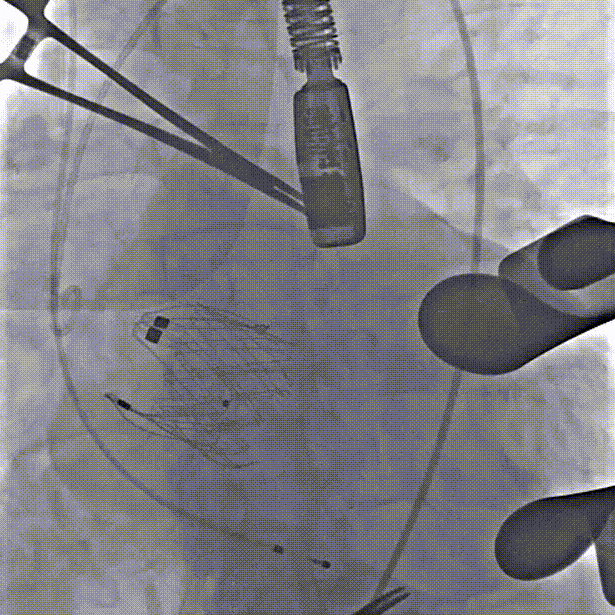

第一枪造影,右窦无窦重合,三窦显示不清

调整角度后造影,右窦居中位置

心尖穿刺建立轨道、单弯导管引导跨弓

定位件跨瓣打开,调整右窦定位件位置,下拉入窦

造影确认定位件入窦底